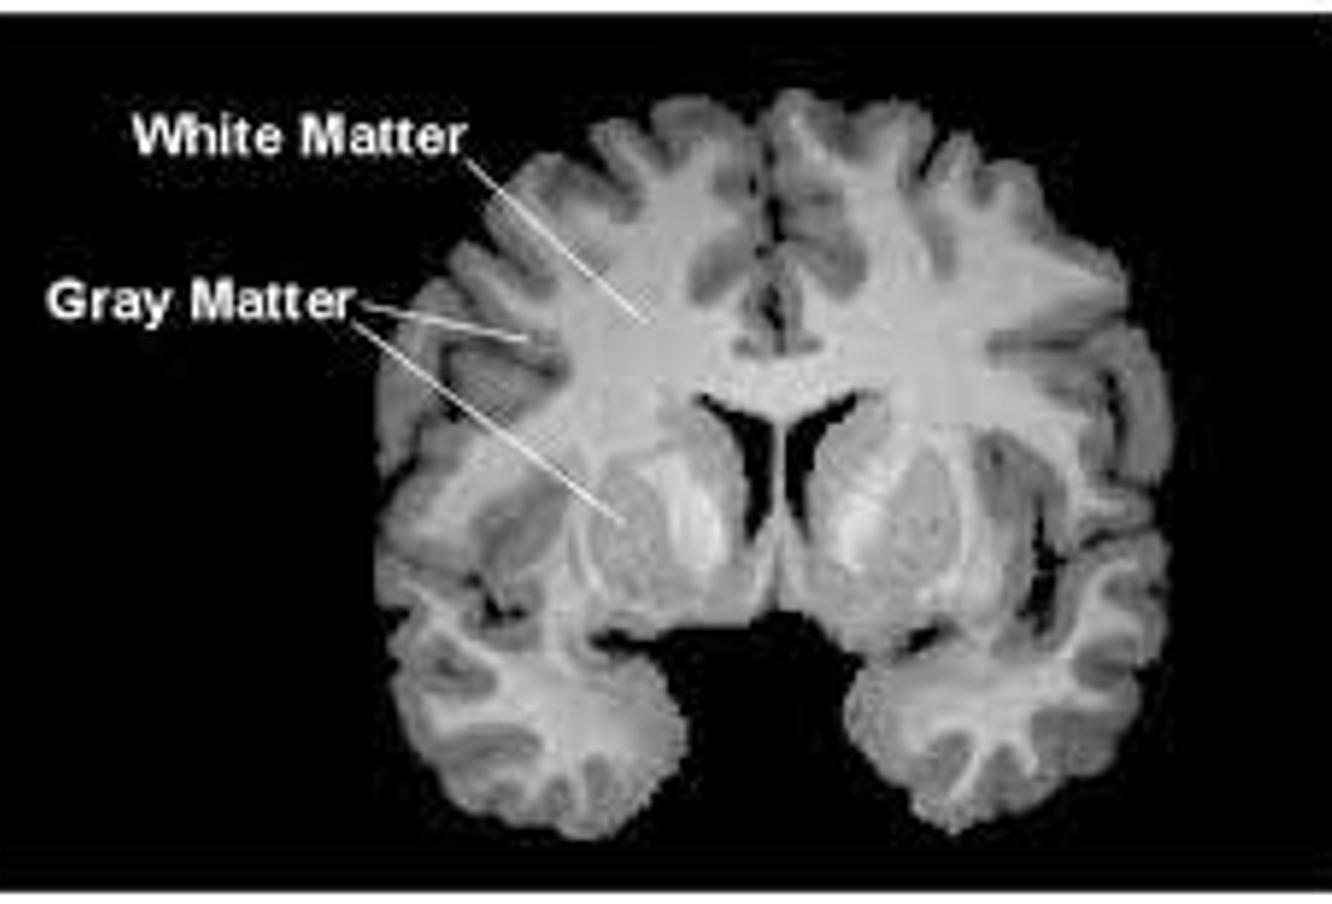

- 대뇌피질을 구성하는 회백질 (Gray Matter) 영역은 뇌 기능 사이에 더욱 명시적인 연관성을 제공합니다. 다음은 피질 및 하위피질 영역으로 구분지어 바라볼 수 있는데, 백색질 (White Matter) 영역에는 이들 사이의 축삭돌기를 포함하고 있습니다.

- 이러한 사실을 바탕으로, 구조적 뇌 네트워크 (Structural Brain Network)는 피질 및 하위피질 영역들 간 연결성 관련한 수학적 모델링 아키텍처로 바라볼 수 있습니다. 다음을 그래프로 표현하는 데 있어서, 노드를 각 영역으로, 엣지들은 백색질 부분을 연결하는 것으로 손쉽게 정의할 수 있습니다.